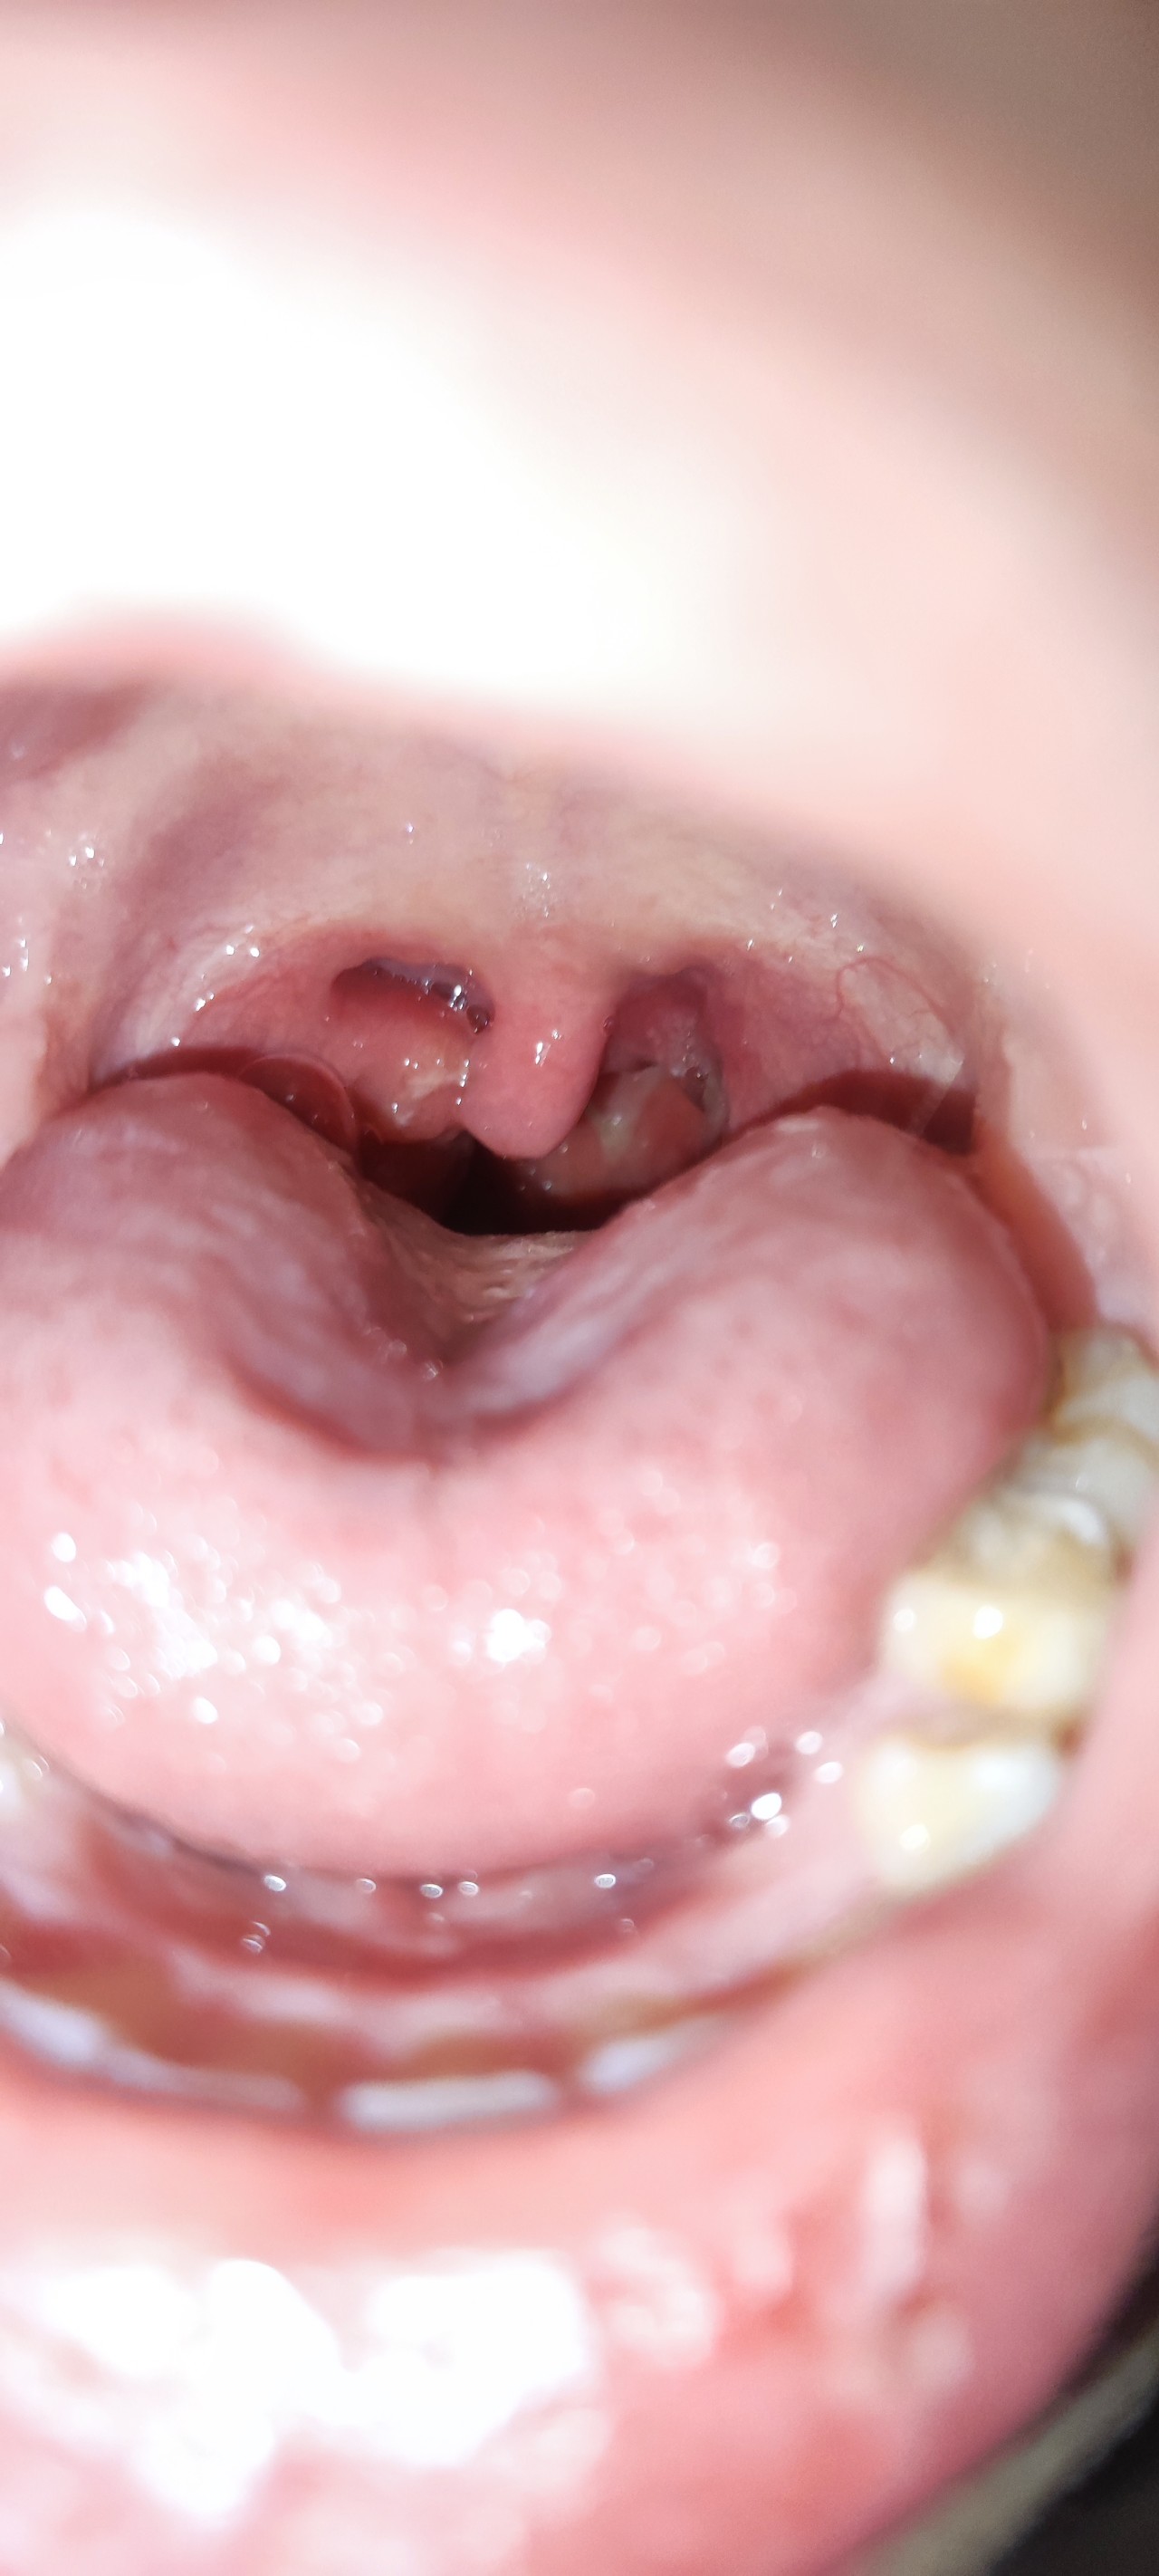

Очень сильная боль в горле, увеличены миндалины

Здравствуйте, вчера ребенок заболел. Была температура и сильная боль в горле. Горло было просто красное, слегка отёчное, как о цчно при ОРВИ, сходили ко врачу, выписали полоскание и граммидин. Ночью температура поднималась до 38.8, сбивала парацетамолом.

Сечас картина в горле немного другая, за 10 лет я у него такого горла не видела, смущает увеличение около небной дужки. Глотать ребенку больно, пить тоже, открывать рот тоже больно. Говорит не было такой боли ни при одном ОРВИ. подскажите пожалуйста, надо ли подкорректировать лечение или пока также полоскать фурацилином и рассасывать граммидин?